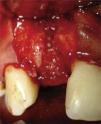

Primer procedimiento- 1.

Extracción de la corona del OD 12 mediante periostótomos y el resto radicular con instrumentos rotatorios (Fresa espiral ACT3015, 3i®) (Figura 4).